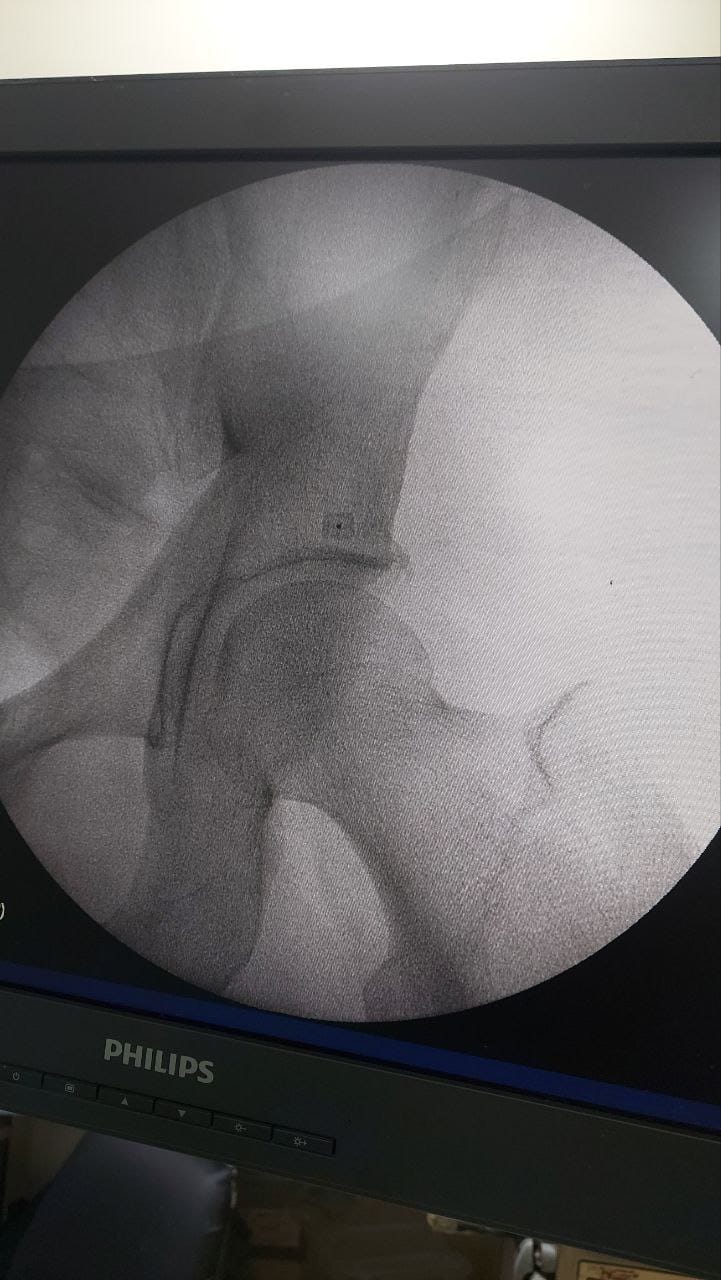

Struggling with chronic pain? Get advanced, personalised pain management from Dr. Manish De, one of Kolkata’s leading pain specialists. From knee pain, heel pain, low back pain, frozen shoulder, migraines, cancer pain to post-TKR persistent pain—Dr. De offers safe, evidence-based treatments across multiple locations: